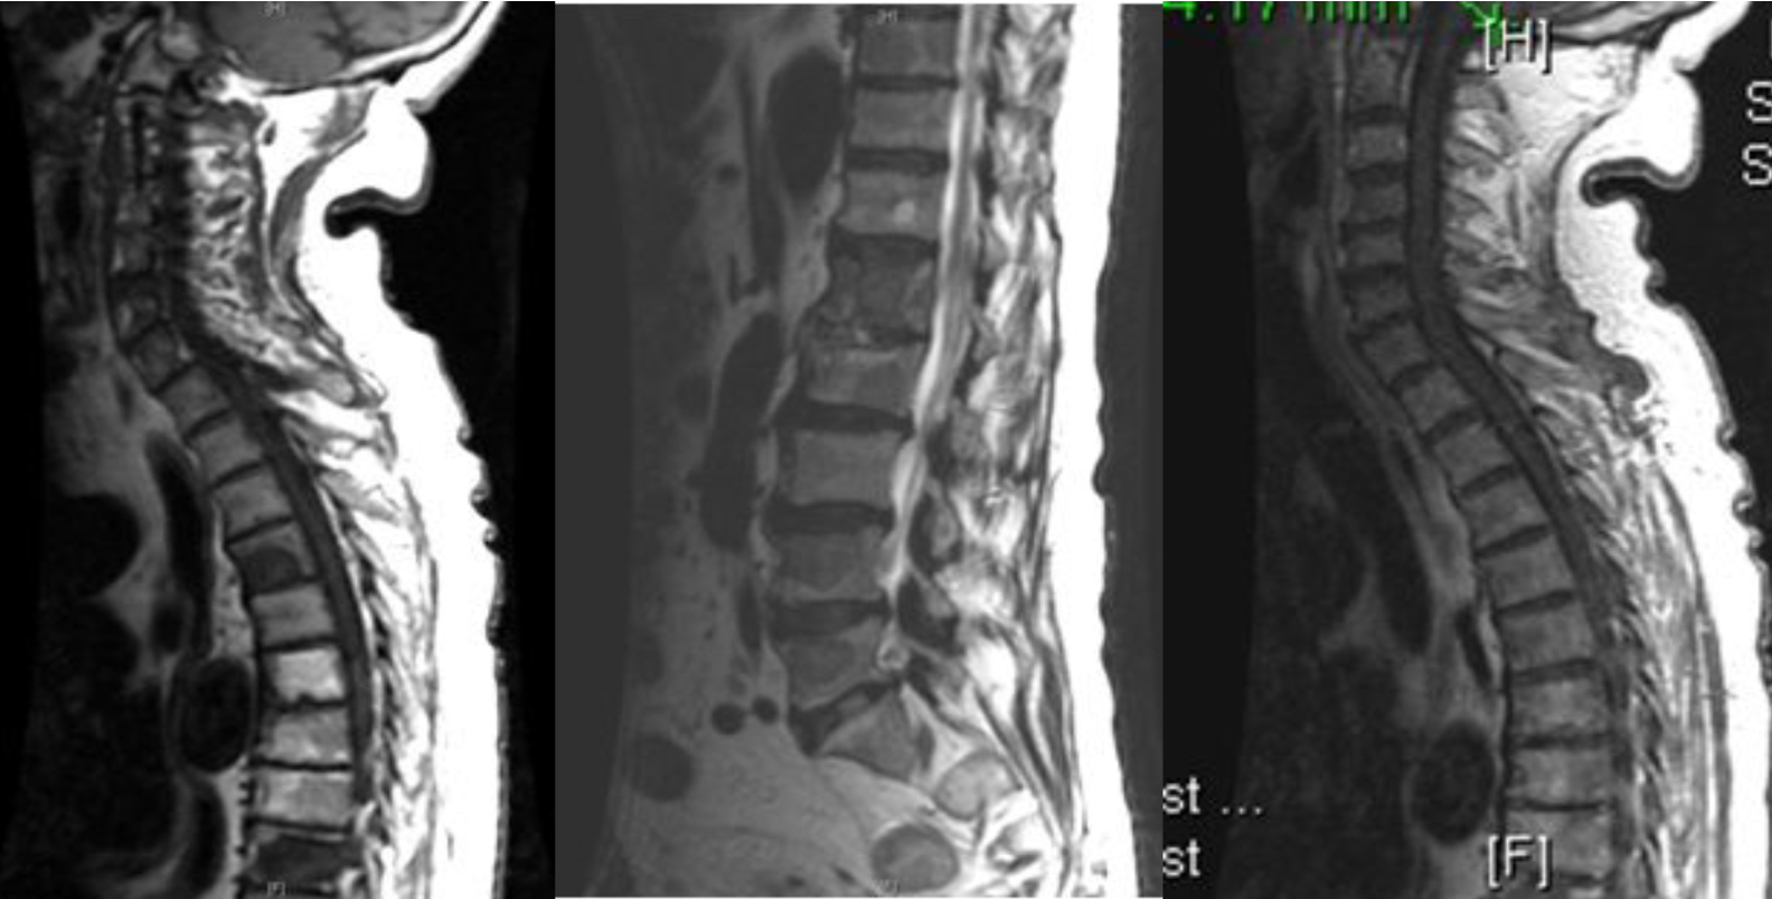

Further work-up revealed an elevated prostate specific antigen (PSA) and acid phosphatase level of 521.20 ng/mL (normal range: 0 - 4 ng/mL) and 70.2 ng/mL (normal range: < 1.5 ng/mL), respectively. A urological consultation was obtained, and prostate biopsy results revealed a poorly differentiated adenocarcinoma with a Gleason score (GS) of 8 and 9 in 11 out of 12 cores, similar to the orbital lesion. Immunohistochemical stains on the orbital tissue (biopsy) were positive for PSA, PSMA, AE1:AE3 and Cam5.2 cytokeratins, and negative for TTF-1, CDX2, CK7, CK20 and EMA. MRI of the spine confirmed multi-level osseous metastatic infiltration throughout the spinal axis particularly involving the lower thoracic and lumbar spine (Fig. 3).

![]() Click for large image | Figure 3. MRI of the spine showing multi-level osseous metastatic infiltration throughout the spinal axis particularly involving the lower thoracic and lumbar regions. |